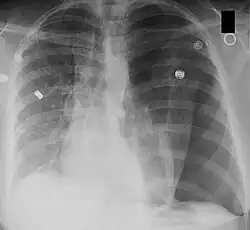

A chest X-ray can rapidly identify a pneumothorax, seen as absence of lung markings. Ultrasound can show the lack of lung sliding. However, imaging should not delay treatment.[8] CT angiography is the standard of diagnosis of pulmonary embolism. Clots appear in the vasculature as filling defects.[18]